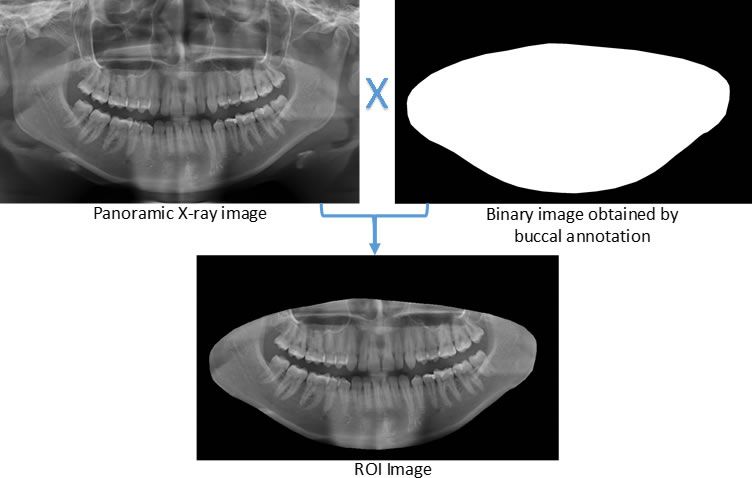

Determining ROI

For each image, after the annotation of the teeth, the buccal region was also annotated, covering the whole region delineated by the contour of the jaws. This process was carried out in view of preserving the area containing all the teeth (objects of interest). Finally, the region of interest (ROI) was determined by multiplying the values of the pixel array elements, representing the original panoramic X-ray image, by its corresponding binary matrix, resulting from the process of oral annotation. Figure 5 illustrates the whole process to determine the ROI of the images.